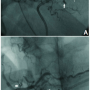

into the same branch during LAD angioplasty. Prolonged balloon inflation at the origin of the culprit vessel did not yield satisfactory result. Therefore, we decided to perform microcoil embolization of the distal LAD. A MiraFlex microcatheter (Cook) with inner diameter of .021-inch was positioned near the origin of the feeding vessel and embolization was performed using an 18-2-2 MCWE HILAL microcoil (Cook). The result was total occlusion of the distal LAD including the culprit branch (Figure 2B). The patient experienced angina of moderate severity, which subsided gradually. About 6 H later, he developed hypotension and echocardiogram revealed re-accumulation of pericardial fluid with evidence of cardiac tamponade. The patient was shifted to the catheterization laboratory, and left coronary angiogram confirmed total occlusion of the distal LAD, and no evidence of reopening of the coronary leak. Pericardiocentesis was continued, which showed aspiration of fresh blood, indicating ongoing bleeding into the pericardial cavity. Therefore, RCA injection was also performed to rule out any leak from the right side. To our surprise, a marginal branch of the RCA was seen supplying the same culprit vessel on left through collateral causing continuous loss of blood (Figure 3A). Selective microcoil embolization of the marginal branch using 18-2-2 MCWE HILAL microcoil (Cook) could successfully close it, resulting in total cessation of blood loss (Figure 3B). Recovery of the patient was mostly uneventful except for transient elevation of serum creatinine level.